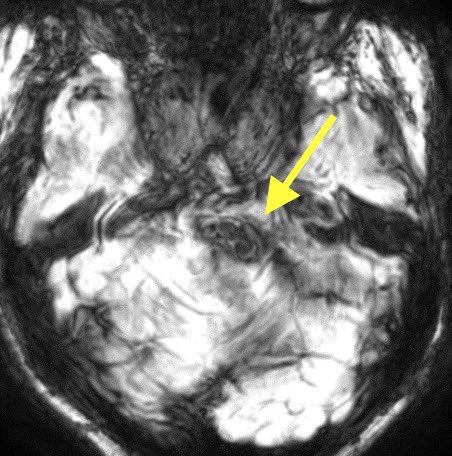

Lesions that disrupt the triangle of Guillain and Mollaret (neural pathway connecting the red nucleus, inferior olivary nucleus, and contralateral dentate nucleus) can result in swollen inferior olivary nuclei

Imaging: T2/FLAIR bright and swollen inferior olivary nuclei w/o enhancement

š” Be aware of HOD to avoid misdiagnosis of tumor, demyelination, etc.